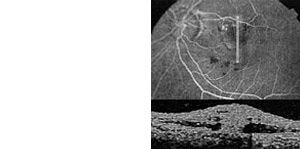

Die automatische Infrarot-Videorefraktion ermöglicht die sekundenschnelle, dynamische, binokulare Messung von Fehlsichtigkeiten und kleinwinkligem Schielen aus einem Meter Entfernung. Diese Untersuchung ist nicht-invasiv;

der Säugling muß zunächst nicht getropft werden.